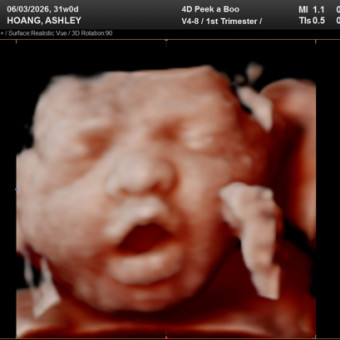

Ashley & Huy's Baby Registry

Ashley Ann & Huy John Hoang

Cantonment, FL

June 3, 2026

After 7 long years of trying, our sweet miracle, Oryn, is finally on the way 🩷